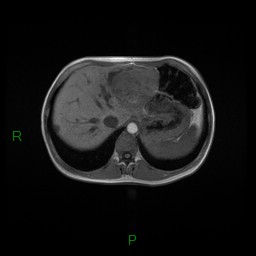

Critères sémiologiques d’hyperplasie nodulaire focale

- Lésion de grande taille, se rehaussant massivement homogène au temps artériel

- Contours nets polylobés

- Jamais d’hémorragie

- Jamais de calcification

- Discret hyperT2 IRM (difficilement visible), avec élément central toujours en hyperT2

- Pdc homogène précoce massive avec homogénéisation, cicatrice fibreuse centrale à Pdc tardive

- Absence de capsule, absence de graisse